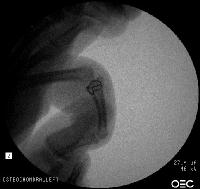

Xrays show an apparently healed PIP fracture dislocation with dorsal subluxation - but concentric tracking of the abnormal palmar articulation.

First impression was that the palmar fragment was probably big enough to take down and reinsert. However, comparison of films shortly after the fracture (above) and at two months (below) confirms the injury as a healed comminuted central impaction fracture with splay and hinging of the volar cortex.